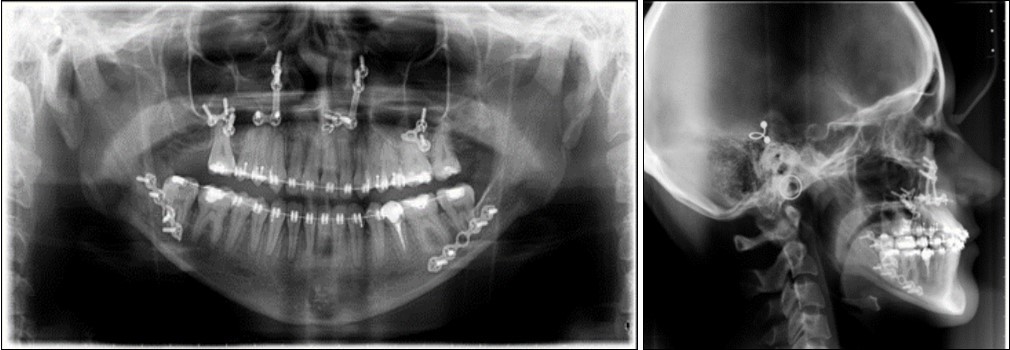

Post-surgical orthodontic treatment was started 4 weeks after the surgery. Wearing of bilateral box elastics was recommended in order to improve interdigitation. (Figure 6) The orthodontic treatment was finished on 0.019x0.025 SS archwires. Post-surgery cephalometric analysis revealed an increase in SNA value by 4 degrees (SNA 82 degrees) and a decrease in SNB value also by 4 degrees (SNB 79 degrees). The patient was now in a skeletal class I, with ANB 3 degrees. An examination of the soft tissue on the radiograph reveales a better relation between the upper and lower lip. (Figure 7).

Figure 7.Post-surgical panoramic and lateral cephalometric radiograph.